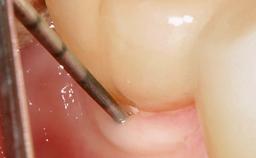

A 72-year-old female patient was referred to the specialist clinic with signs of peri-implantitis associated with implant 14. Two implants (sites 14 and 15) had been in function for three years. The patient was in good general health and was not taking any medication. She was a former smoker (12–15 cigarettes a day for 50 years) but had ceased smoking two years prior to implant placement. Her periodontal condition was stable, with no probing depths above 5 mm and a full-mouth plaque score (FMPS) of 35%.